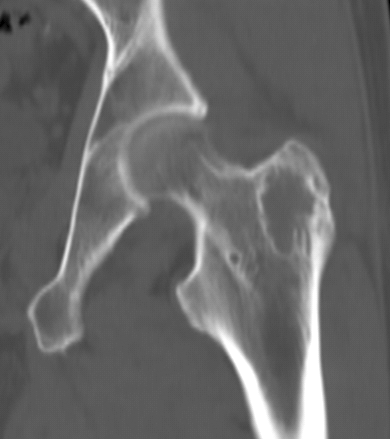

图 3.地图样破坏:骨内脂肪瘤

图片

营养不良性钙化

营养不良性钙化为局部钙盐代谢异常所致的钙化。X 线平片和 CT 表现为无结构的不规则形致密影。良性肿瘤常见于骨内脂肪瘤(图 39),恶性骨肿瘤则常见于 PNET(图 40)和未分化多形性肉瘤。

图 39.营养不良性钙化:骨内脂肪瘤